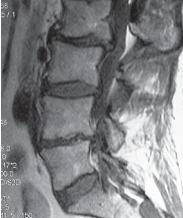

МРТ № 3

На МРТ № 3 — поясничный отдел позвоночника. (На данном «контрольном» снимке наблюдаются остаточные явления дегенеративно-дистрофического процесса в сегменте LV-SI после устранения методом вертеброревитологии секвестрированной грыжи межпозвонкового диска.)

В поясничном отделе форма позвоночного канала, создаваемая телом и дужками позвонка, вариабельна, но чаще она пятиугольная. В норме позвоночный канал в пояснично-крестцовом отделе сужен в переднезаднем диаметре на уровне LIII и LIV позвонков. Его диаметр каудально увеличивается, и поперечное сечение канала приобретает форму, близкую к треугольной, на уровне LV-SI. У женщин канал имеет тенденцию к расширению в нижней части крестцовой области. Сагиттальный диаметр значительно уменьшается от LI к LIII почти неизменен от LIII к LIV и увеличивается от LIV к LV. В норме переднезадний диаметр позвоночного канала в среднем равен 21 мм (15–25 мм).

Существует простая и удобная формула определения ширины позвоночного канала:

нормальный сагиттальный размер не менее 15 мм;

11–15 мм — относительный стеноз;

менее 10 мм — абсолютный стеноз. Уменьшение этого соотношения свидетельствует о сужении канала.

Высота поясничных межпозвонковых дисков 8–12 мм, нарастает от LI до LIV-LV, обычно уменьшается на уровне LV-SI